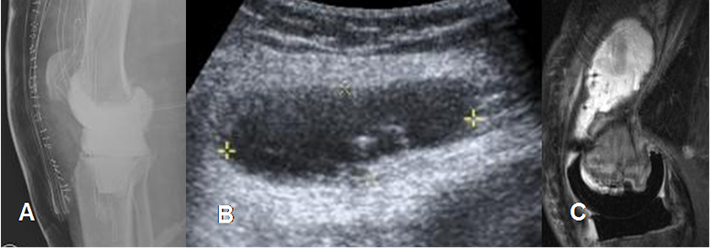

Fig 207 A. Seroma.

A: Rx AP. Paciente con múltiples cirugías abdominales, a la que se le colocó una malla abdominal.

B y C: Ecografías. En el PostQx aparecen cambios inflamatorios en la cicatriz Qx y se identifica colección líquida, con ecos y septos en su interior, que corresponde a seroma.

Fig 207 C. Seroma.

A: RM axial en T2, B: RM sagital en T2 y C: RM sagital en STIR. Signos de laminectomía derecha, por hernia de disco en A. Se encuentra colección líquida en los tejidos blandos, por la formación de seroma.